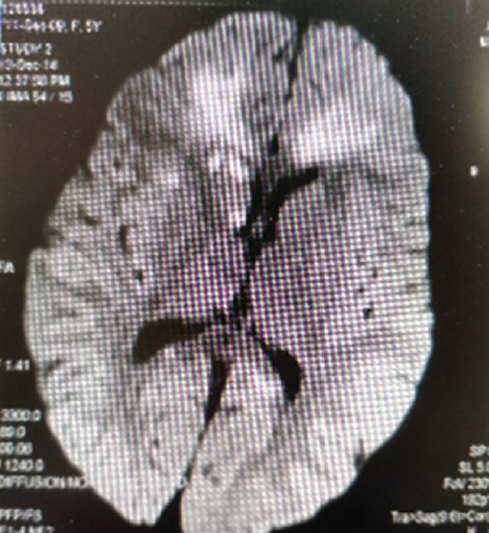

In this study, 23 % of pediatric patients with PM of hemophilic and meningococcal etiologies had foci of pathological MR signal caused by vasculitis with multiple small ischemic zones of various sizes, round or oval in shape, with indistinct contours, which were localized in both the subcortical and periventricular regions of the white matter (Fig. 1). DWI MRI in 63 % of children showed multiple bilateral foci of infarcts, most likely due to small-vessel vasculitis (Fig. 2).

Fig. 2. MRI of a child, 2,4 years old. The DWI shows multiple infarctions of the corpus callosum and the right caudate nucleus / Рис. 2. Магнитно-резонансная томограмма головного мозга ребенка, 2 года 4 мес. На DWI множественные инфаркты мозолистого тела и правого хвостатого ядра